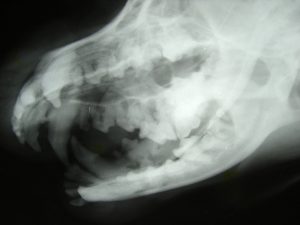

One way we do this is by offering digital dental radiographs. Taking radiographs during dental procedures allows veterinarians to correctly diagnose dental problems. It allows us to look inside your pet’s teeth and see their oral cavities. Digital dental radiographs allow us to decide which teeth need to be pulled and which are healthy enough to stay. They also help us decide if owners need to do more for their pets at home.

Digital radiographs are very safe and effective. We will be able to view the radiographs just seconds after they are taken, so they are an invaluable diagnostic tool during dental cleanings.